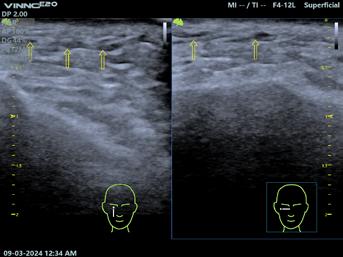

Fig.2. Ecocardiografie transtoracică – pacient sever simptomatic cu cardiomiopatie hipertrofică. (A) Sept interventricular cu hipertrofie extremă. (B) Mișcare sistolică anterioară a valvei mitrale (SAM) și contact mitro-septal. (C) Contact mitro-septal prelungit în timpul sistolei (mod M). (D) Gradient de circa 130 mmHg în tractul de ejecție al ventriculului stâng (Doppler). Adaptat după [15]

Este esențial ca evaluările ecocardiografice să fie făcute diligent și după un protocol standard, orientarea și alinierea în planuri ortogonale trebuie să fie corecte pentru a măsura corespunzător structurile cardiace. Protocolul standard este util mai ales pentru că hipertrofia din CMH, deși interesează cel mai frecvent septul bazal, poate interesa orice segment ventricular (SIV posterior, apex VS, perete lateral)[12]. Se urmăresc parametri ca funcția sistolică și diastolică a VS, hipertrofia VS, prezența sau absența obstrucției în TEVS, volumul atriului stâng (AS), precum și date despre morfologia și funcția aparatului mitral.

Estimarea grosimii peretelui VS se face din mai multe incidențe, la sfârșitul diastolei, în secțiuni ax scurt, evitând secțiunile oblice care supraestimează hipertrofia ventriculară. Secțiunea parasternală ax lung, în modul M, ar trebui evitată pentru efectuarea măsurătorilor[13]

Conform ghidurilor de specialitate, tuturor pacienților diagnosticați cu CMH le este recomandată efectuarea ecocardiografiei 2D și Doppler, atât în repaus, cât și în timpul manevrei Valsalva – dacă gradientul de repaus este sub 50 mmHg și pacientul este simptomatic.

În cadrul urmăririi cardiologice de rutină, parte a îngrijirii optime este efectuarea de ecocardiografii transtoracice seriate. La pacienții asimptomatici, ETT se recomandă a fi repetată o dată la 1-2 ani, urmărindu-se modificări ale funcției sistolice și diastolice a VS, gradul de hipertrofie, obstrucția din TEVS, boli valvulare concomitente. Intervalul ar putea fi extins dacă pacientul rămâne clinic stabil după multiple evaluări[6]

Fiziopatologia care contribuie la obstrucția TEVS (Fig.2) include anomalii interconectate precum hipertrofia asimetrică a VS, SAM, hipertrofia mușchilor papilari cu sau fără deplasarea acestora, inserții anormale ale mușchilor papilari, cât și modificări la nivelul cuspelor valvei mitrale (VM)[14]

Fig.3. Ecocardiografie transesofagiană în cardiomiopatie hipertrofică obstructivă, ce remarcă obstrucția tractului de ejecție al ventriculului stâng (VS) prin contact mitro-septal (sus, săgeată) și regurgitare mitrală importantă (jos) ETE efectuată perioperator (Fig.3) este însă esențială pentru ghidarea strategiei chirurgicale în cazul miectomiei chirurgicale,

evaluarea rezultatelor acesteia și la identificarea eventualelor complicații intraoperatorii (obstrucție sau regurgitare mitrală reziduală, defect septal ventricular iatrogen, regurgitare aortică)[17]